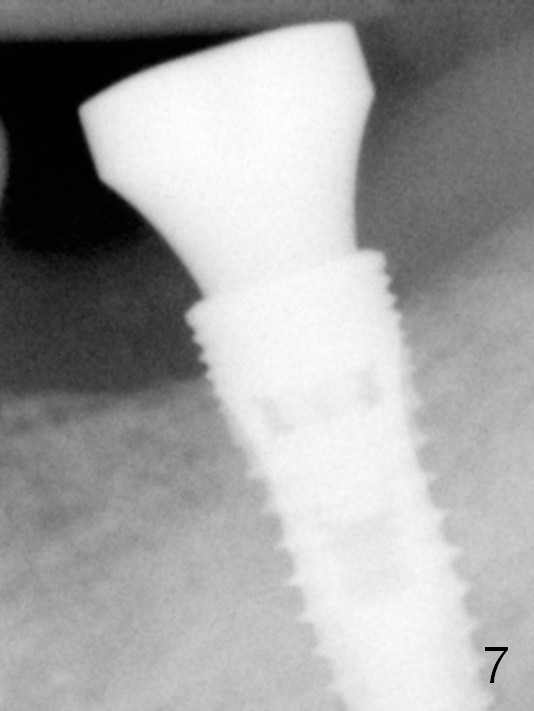

The 1st 4 coronal threads remains outside the bone 3.5 months postop (Fig.7). It appears that less thread exposure (3 instead) 1 year 7 months postop (Fig.8), suggesting bone growth.